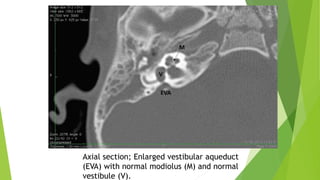

7- Enlarged Vestibular

Aqueduct (EVA)

Enlarged Vestibular Aqueduct (EVA)

presence of an enlarged vestibular aqueduct (i.e. the midpoint between posterior labyrinth

and operculum is larger than 1.5 mm) in the presence of a normal cochlea, vestibule and

SCCs.

Difference between EVA and IP-II is that cochlea and vestibule are completely normal on

HRCT and MRI.

Classically EVA is described when the midpoint between posterior labyrinth and operculum

is larger than 1.5 mm on axial sections.“vertical and axial width larger than 1.5 mm on the

midpoint between labyrinth and operculum”

Audiological presentation and management is similar to that of IP-II.

Axial section; Enlarged vestibular aqueduct

(EVA) with normal modiolus (M) and normal

vestibule (V).